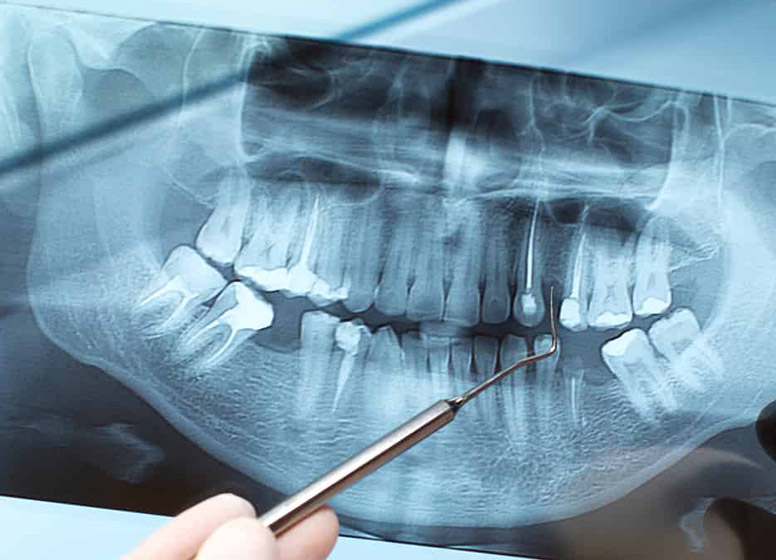

Radiografia digitală retroalveolară dentară este o radiografie digitală care se realizează la unul, maxim doi dinţi. Această radiografie permite medicului stomatolog să vadă în detaliu coroana şi rădăcina întregului dinte, la dimensiuni reale. De obicei această radiografie este indicată când se face un tratament endodontic (se scoate nervul) sau pentru o rezecţie apicală (operaţia rădăcinii dintelui).